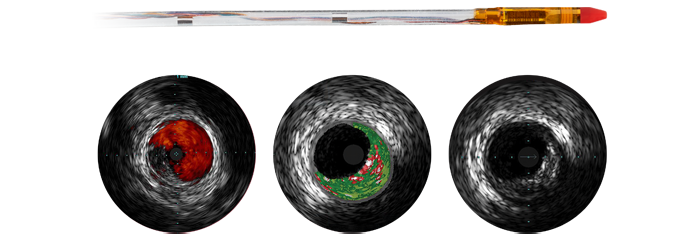

A medida que se considera la posibilidad de someter a más pacientes con coronariopatías a tratamientos intervencionistas mínimamente invasivos, la planificación de los mismos se ve obstaculizada por las limitaciones de la angiografía coronaria en 2D para detectar y evaluar la estenosis coronaria. Los datos no están conectados de manera coherente y significativa antes y durante el procedimiento, lo que añade tiempo y complejidad a la planificación del tratamiento. Hemos diseñado nuestras soluciones de cardiología de modo que pueda obtener las ventajas de la eficacia clínica en el laboratorio de cateterismo:

La terapia guiada por imagen, iFR, los ultrasonidos intravasculares y la monitorización hemodinámica, así como la planificación previa al procedimiento cardiaco y las aplicaciones avanzadas, están conectados a la interfaz de la terapia guiada por imagen para permitir la visualización, manipulación y configuración personalizada en el monitor desde un único módulo de control en mesa o desde la sala de control.